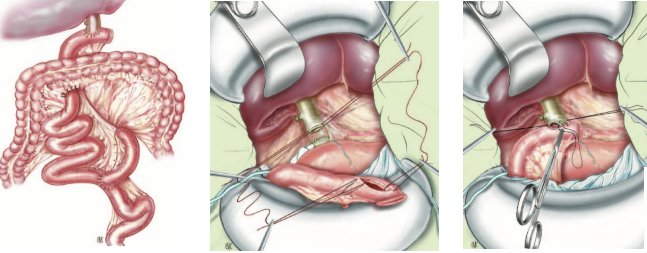

- Nối mật ruột: Đối với sỏi mật tái phát nhiều lần do có hẹp đoạn xa OMC, hoặc sỏi mật trong gan tái phát di chuyển nhiều lần:

- Nối OMC-tá tràng bên-bên:

- Nối OMC (hoặc ống gan chung) – hỗng tràng kiểu Roux-en-Y :

- Nối mật-ruột với quai ruột dưới da

Hình. Nối OMC-tá tràng qua quai hỗng tràng biệt lập

Hình. Nối ống gan chung-hỗng tràng trên quai Y. Đầu tận quai hỗng tràng đưa dưới da để dàng can thiệp sỏi trong gan tái phát di chuyển.